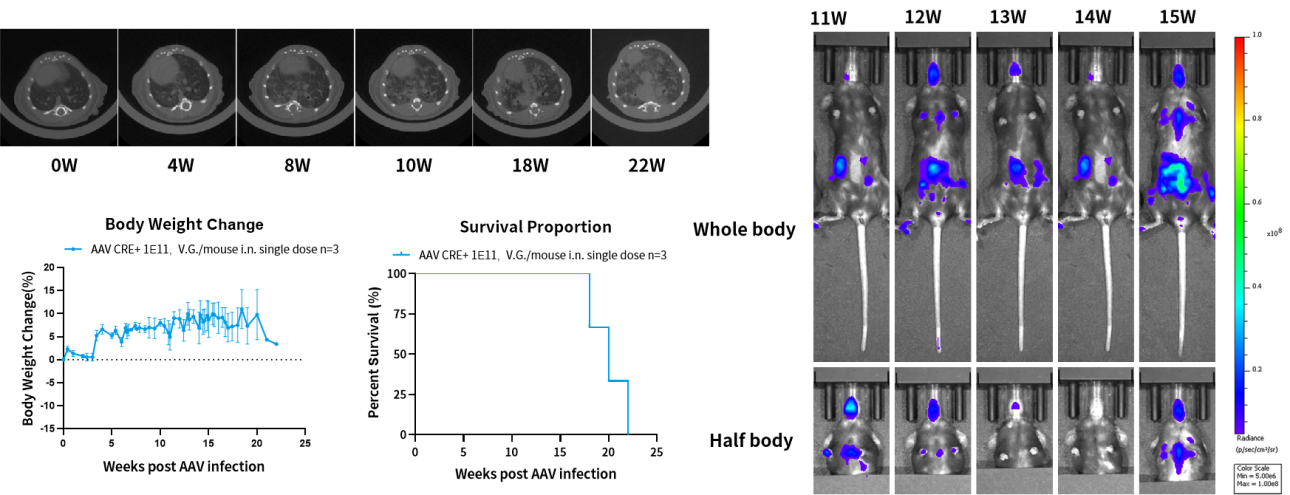

小鼠背景:C57BL/6

Ki67蛋白被广泛用作肿瘤标志物,并且 Ki67指数与肿瘤疾病的病程相关,可用于评估患者生存和癌症进展。南模生物将Mki67-tdTomato-2A-Luc小鼠与Kras-LSL-G12D小鼠进行交配,并通过AAV注射诱导KrasG12D/Mki67-Akaluc基因型小鼠形成肿瘤。

验证数据:

图4. Mki67-tdTomato-2A-Luc原发肺癌小鼠模型可通过AAV-CRE诱导引发肺癌。